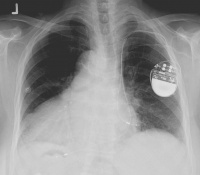

(5) [2] Röntgenbild eines Brustkobes mit Herzschrittmacher